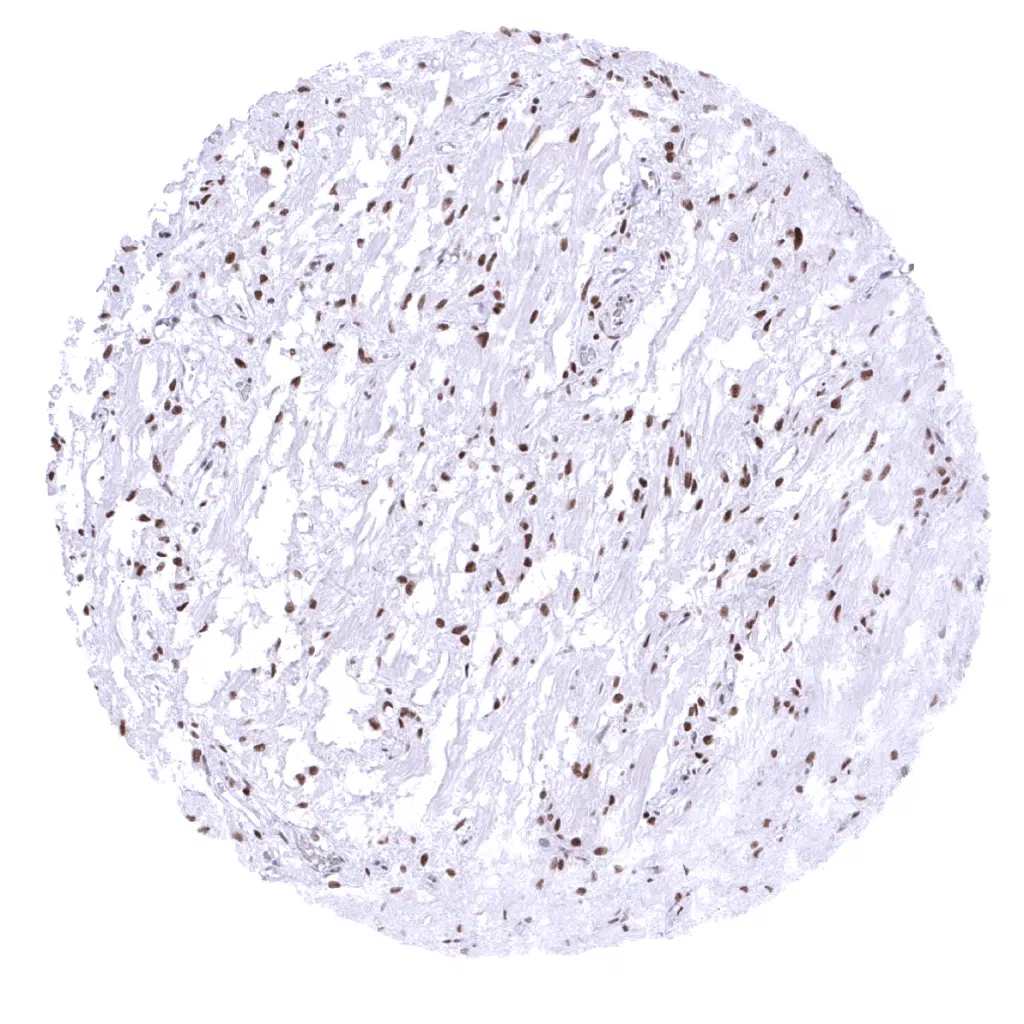

Uterus, myometrium